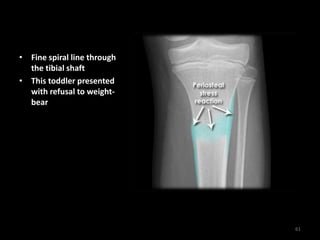

• Fine spiral line through

the tibial shaft

• This toddler presented

with refusal to weight-

bear